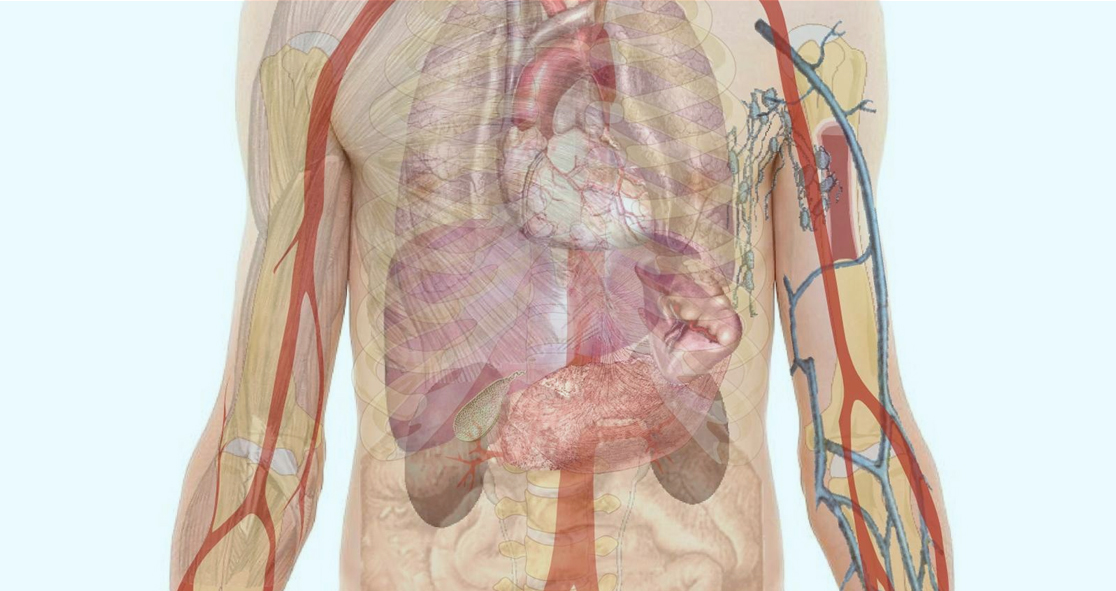

Thermogenesis is a process in which brown fat burns energy and generates heat after getting activated by chemical signals or cold temperatures.

Humans are known to have small deposits of brown fat, and researchers opine that findings ways to pharmacologically activate this fat could improve metabolism.

The study researchers have discovered that human brown fat cells contain beta2-adrenergic receptors (b2-AR) that are responsible for stimulating thermogenesis.

“We show that perhaps we were aiming for the wrong target all along,” he said. “In contrast to rodents, human BAT is activated through the stimulation of the beta2-adrenergic receptor, the same receptor responsible for the release of fat from our white adipose tissue.”

“Activation of brown fat burns calories improves insulin sensitivity and even affects appetite regulation,” Prof. Schéele said. “Our data reveals a previously unknown key to unlocking these functions in humans, which would potentially be of great gain for people living with obesity or type 2 diabetes.”